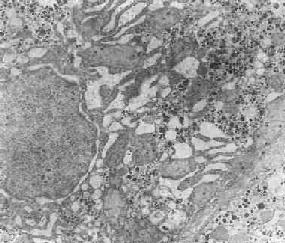

三、内质网除红细胞外,内质网或多或少地见于所有各种细胞。内质网为由生物膜构成的互相通连的片层隙状或小管状系统,膜片间的隙状空间称为池,通常与细胞外隙和细胞浆基质之间不直接相通。这种细胞内的膜性管道系系一方面构成细胞内物质运输的通路,另方面为细胞内各种各样的酶反应提供广阔的反应面积。内质网与高尔基体及核膜相连续。 (一)粗面内质网 在病理状态下,粗面内质网(RER)可发生量和形态的改变。在蛋白质合成及分泌活性高的细胞(如浆细胞、胰腺腺泡细胞、肝细胞等)以及细胞再生和病毒感染时,粗面内质网增多。粗面肉质岗的含量高低也常反映肿瘤细胞的分化程度。相反,在萎缩的细胞(如饥饿时)以及有某种物质贮积的细胞,其粗面内质网则萎缩、减少。当细胞受损时,粗面内质网上的核蛋白体往往脱落于胞浆内,粗面内质网的蛋白合成乃下降或消失;当损伤恢复时,其蛋白合成也随之恢复。 在由各种原因引起的细胞变性和坏死过程中,粗面内质网的池一般出现扩张,较轻的和局限性的扩张只有在电镜下才能窥见,重度扩张时则在光学显微镜下可表现为空泡形成,电镜下有时可见其中含有中等电子密度的絮状物。在较强的扩张时,粗面内质网同时互相离散,膜上的颗粒呈不同程度的脱失。进而内质网本身可断裂成大小不等的片段和大小泡(图1-6)。这些改变大多见于细胞水肿时,故病变不仅见于内质网,也同时累及Golgi器、线粒体和胞浆基质,有时甚至还累及溶解体。

图1-6肝细胞粗面内质网扩张 (二)光面内质网 光面内质网的功能多种多样,即参与糖原的合成,又能合成磷脂、糖脂以及糖蛋白中的糖成分,此外,还在甾类化合物的合成中起重要的作用,故在合成甾类激素的细胞中特别丰富。光面内质网含有脱甲基酶、脱羧酶、脱氨酶、葡糖醛酸酶以及混合功能氧化酶等,因而光面内质网能分解甾体、能灭活药物和毒物并使其能被排除(如肝细胞)。肠上皮细胞的光面内质网参与脂肪的运输,心肌细胞的光面内质网(肌浆网)则参与心肌的刺激传导。 在生理状态下,随着细胞功能的升降,光面内质网(SER)的数量也呈现相应改变。但亦可出现完全相反的情况,例如在某些疾病(如淤胆)时,从形态结构上看,肝细胞光面内质网显著增生(图1-7),但其混合功能氧化酶的活性反而下降,这实际上是细胞衰竭的表现。 肝细胞的光面内质网具有生物转化作用(biotransformation),能对一些低分子物质如药物、毒品、毒物等,进行转化解毒,并将间接胆红素转化为直接胆红素。 许多成瘾药物和嗜好品如巴比妥类、吸毒、嗜酒等,可导致肝细胞光面内质网的增生,长期服用口服避孕药、安眠药、抗糖尿病药等也能导致同样后果。在HBsAg阳性肝炎时,肝细胞内光面内质网明显增生,在其管道内形成HBsAg。由于光面内质网的大量增生,这种肝细胞在光学显微镜下呈毛玻璃外观,故有毛玻璃细胞之称,并可为地衣红(orcein)着染。 在细胞损伤时光面内质网也可出现小管裂解为小泡或扩大为大泡状。在药物及某些芳香族化合物(主为致癌剂)的影响下,光面内质网有时可在胞浆内形成葱皮样层状结构,即“副核”,可为细胞的适应性反应(结构较松)或为变性性改变(结构致密)。